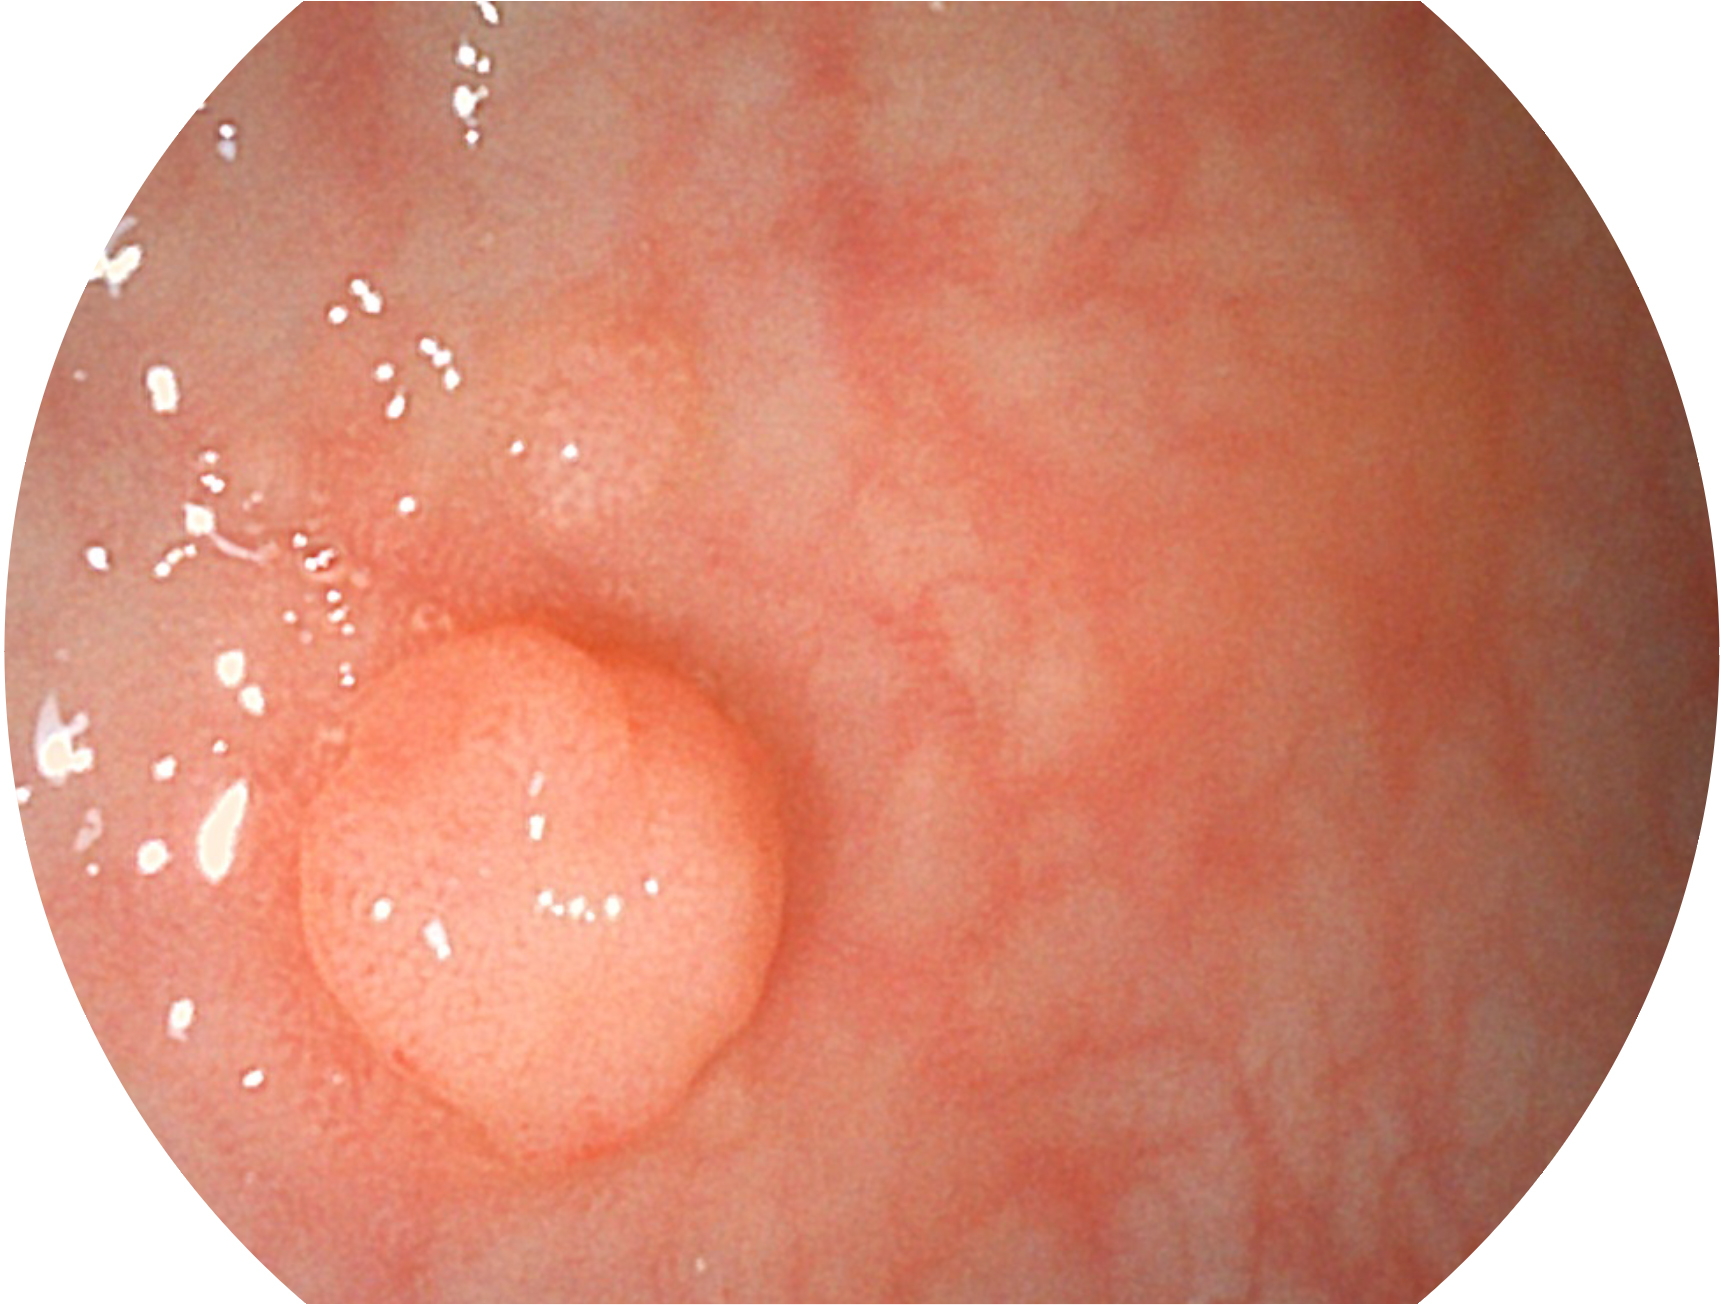

db真人体育官网新开发的内镜染色技术,主要是基于多波长LED 光源的开发,VLS-55Q 四波长LED 光源是由四个不同颜色的LED光按照相应照明模式所规定的特定发光比例进行合束后形成,合束后形成的照明光的光谱由红光、绿光、蓝光及蓝紫光这四个不同的波段范围构成。具有更高光谱自由度,通过光谱比例的控制,实现了聚谱成像技术,英文全称为“Spectral Focused Imaging, SFI”,缩写为“SFI”和光电复合染色成像技术,英文全称为“Versatile Intelligent Staining Technology, VIST”,缩写为“VIST”。